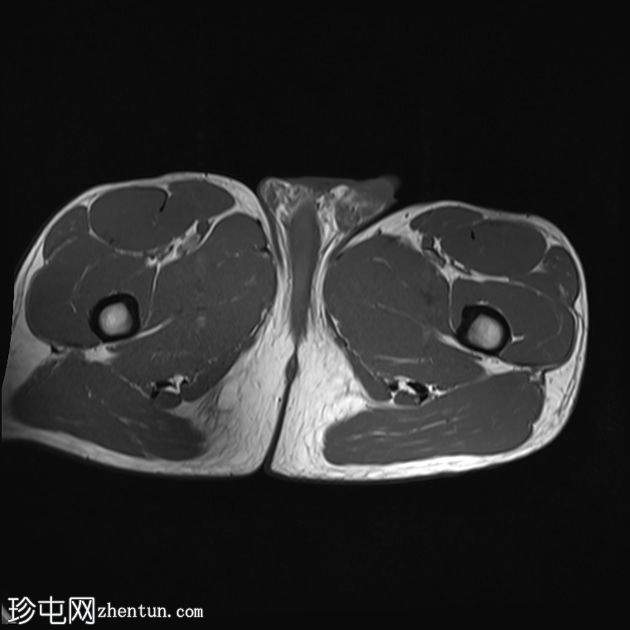

5.jpg

轴位

T2加权像

股直肌近端和中段前外侧可见一水肿性高信号影,长约15厘米,宽约3厘米。肌纤维轻度分离,但未见撕裂。肌内未见积液;在相邻肌间隙可见一条细小的液线环绕肌肉,延伸至近端肌腱交界处。

股直肌中段的间接肌腱轻度增厚,伴有肌腱周围水肿,提示2B级拉伤。但肌腱保持连续性,骨性附着良好,未见撕裂。